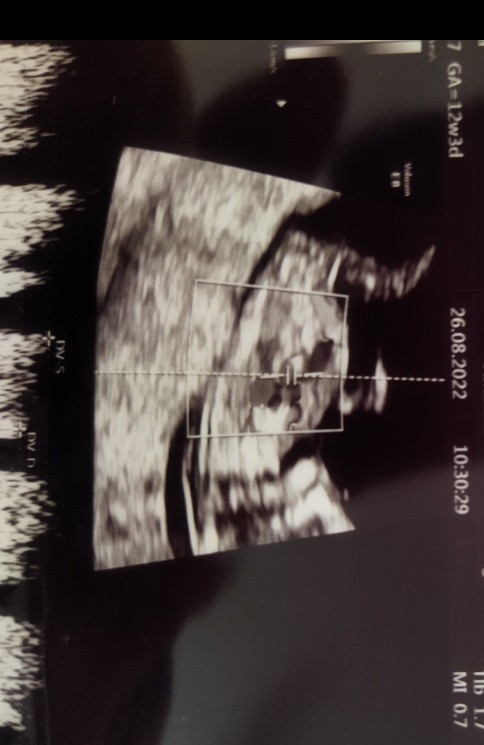

Hej. W 12 tc mialam prenatalne. Jedno zdjecie maluszka 2d bylo male, ale widac je chyba w całości. Czy na tym zdjeciu widac wyrostek płciowy? A jesli tak to jaki jest zgodnie z teoria nub? Myślę, że powinnam sie dowiedzieć w sumie na polowkowym, ale wiadomo jestsem ciekawa.

• IMG_20220827_105503.jpg

56,4 KB · Wyświetleń: 642